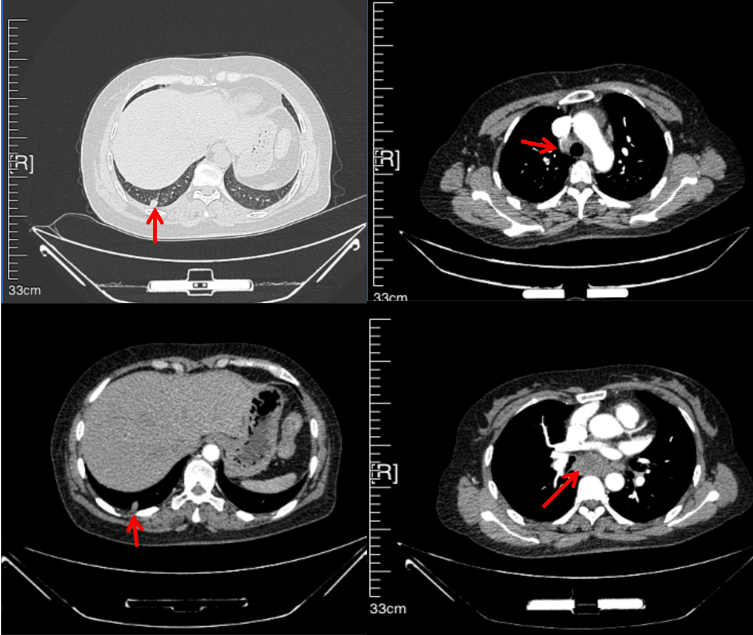

56岁,女性,无吸烟史饮酒史,既往体健。2023年02月患者体检发现肺占位性病变,胸部增强CT:右肺下叶后基底段结节;右侧锁骨上及纵隔内多发淋巴结肿大。PET-CT:右肺下叶周围型肺癌可能性大;1R、2L、3P、4R、4L及7组淋巴结转移可能性大。2023年02月就诊于本院胸外科行超声胃镜下纵隔肿物穿刺活检术,病理:结合免疫组化,符合肺腺癌。行NGS基因检测:EML4:exon20-ALK:exon20融合。PD-L1(克隆号22C3)TPS=55%。

临床诊断:右肺下叶恶性肿瘤cT1bN3M0,IIIB(第9版分期),纵隔淋巴结继发恶性肿瘤,锁骨上淋巴肿继发恶性肿瘤

治疗经过:2023年3月27日始行恩沙替尼靶向治疗至今,最佳疗效为PR,末次评效为维持PR。期间出现轻度肝功能异常(DILI 1级),对症处理后好转。截止目前PFS为26个月。

2023年2月20日基线检查

2024年6月复查PR(最佳疗效)

2024年12月复查维持PR

2025年3月复查维持PR